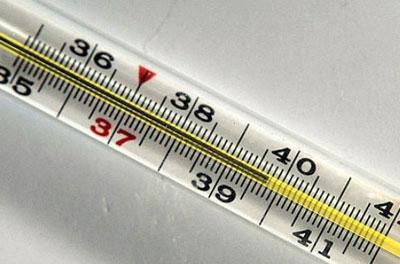

- Высокая температура тела не спадает в течение двух дней. При этом прием жаропонижающих препаратов не оказывает никакого эффекта.

- Повышение температуры тела.